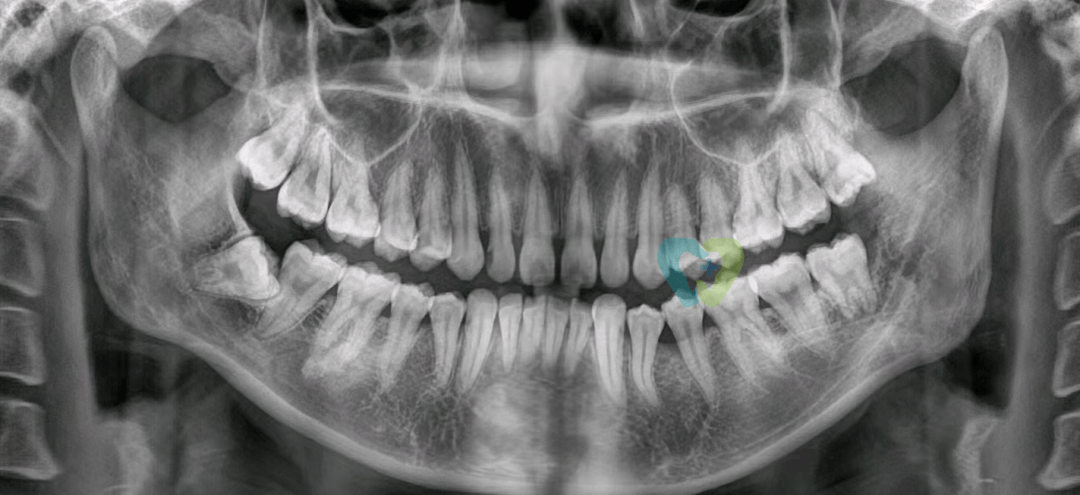

文章图片

阻生智齿 , 图源:网络

检查发现其左下智齿部分萌出 , 颌面大面积龋坏 , 盲袋较深 。 全景片显示 , 小七共有4颗智齿 , 左侧上颌智齿垂直低位阻生 , 左侧下颌智齿垂直高位阻生 , 右侧上颌智齿颊向低位阻生 , 而右侧下颌智齿近中低位阻生 。 患者要求将4颗智齿都拔除 。

术前全景片